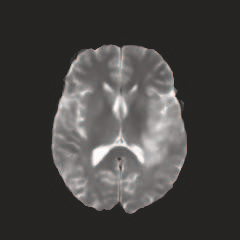

Multi-modal medical image completion has been extensively applied to alleviate the missing modality issue in a wealth of multi-modal diagnostic tasks. However, for most existing synthesis methods, their inferences of missing modalities can collapse into a deterministic mapping from the available ones, ignoring the uncertainties inherent in the cross-modal relationships. Here, we propose the Unified Multi-Modal Conditional Score-based Generative Model (UMM-CSGM) to take advantage of Score-based Generative Model (SGM) in modeling and stochastically sampling a target probability distribution, and further extend SGM to cross-modal conditional synthesis for various missing-modality configurations in a unified framework. Specifically, UMM-CSGM employs a novel multi-in multi-out Conditional Score Network (mm-CSN) to learn a comprehensive set of cross-modal conditional distributions via conditional diffusion and reverse generation in the complete modality space. In this way, the generation process can be accurately conditioned by all available information, and can fit all possible configurations of missing modalities in a single network. Experiments on BraTS19 dataset show that the UMM-CSGM can more reliably synthesize the heterogeneous enhancement and irregular area in tumor-induced lesions for any missing modalities.